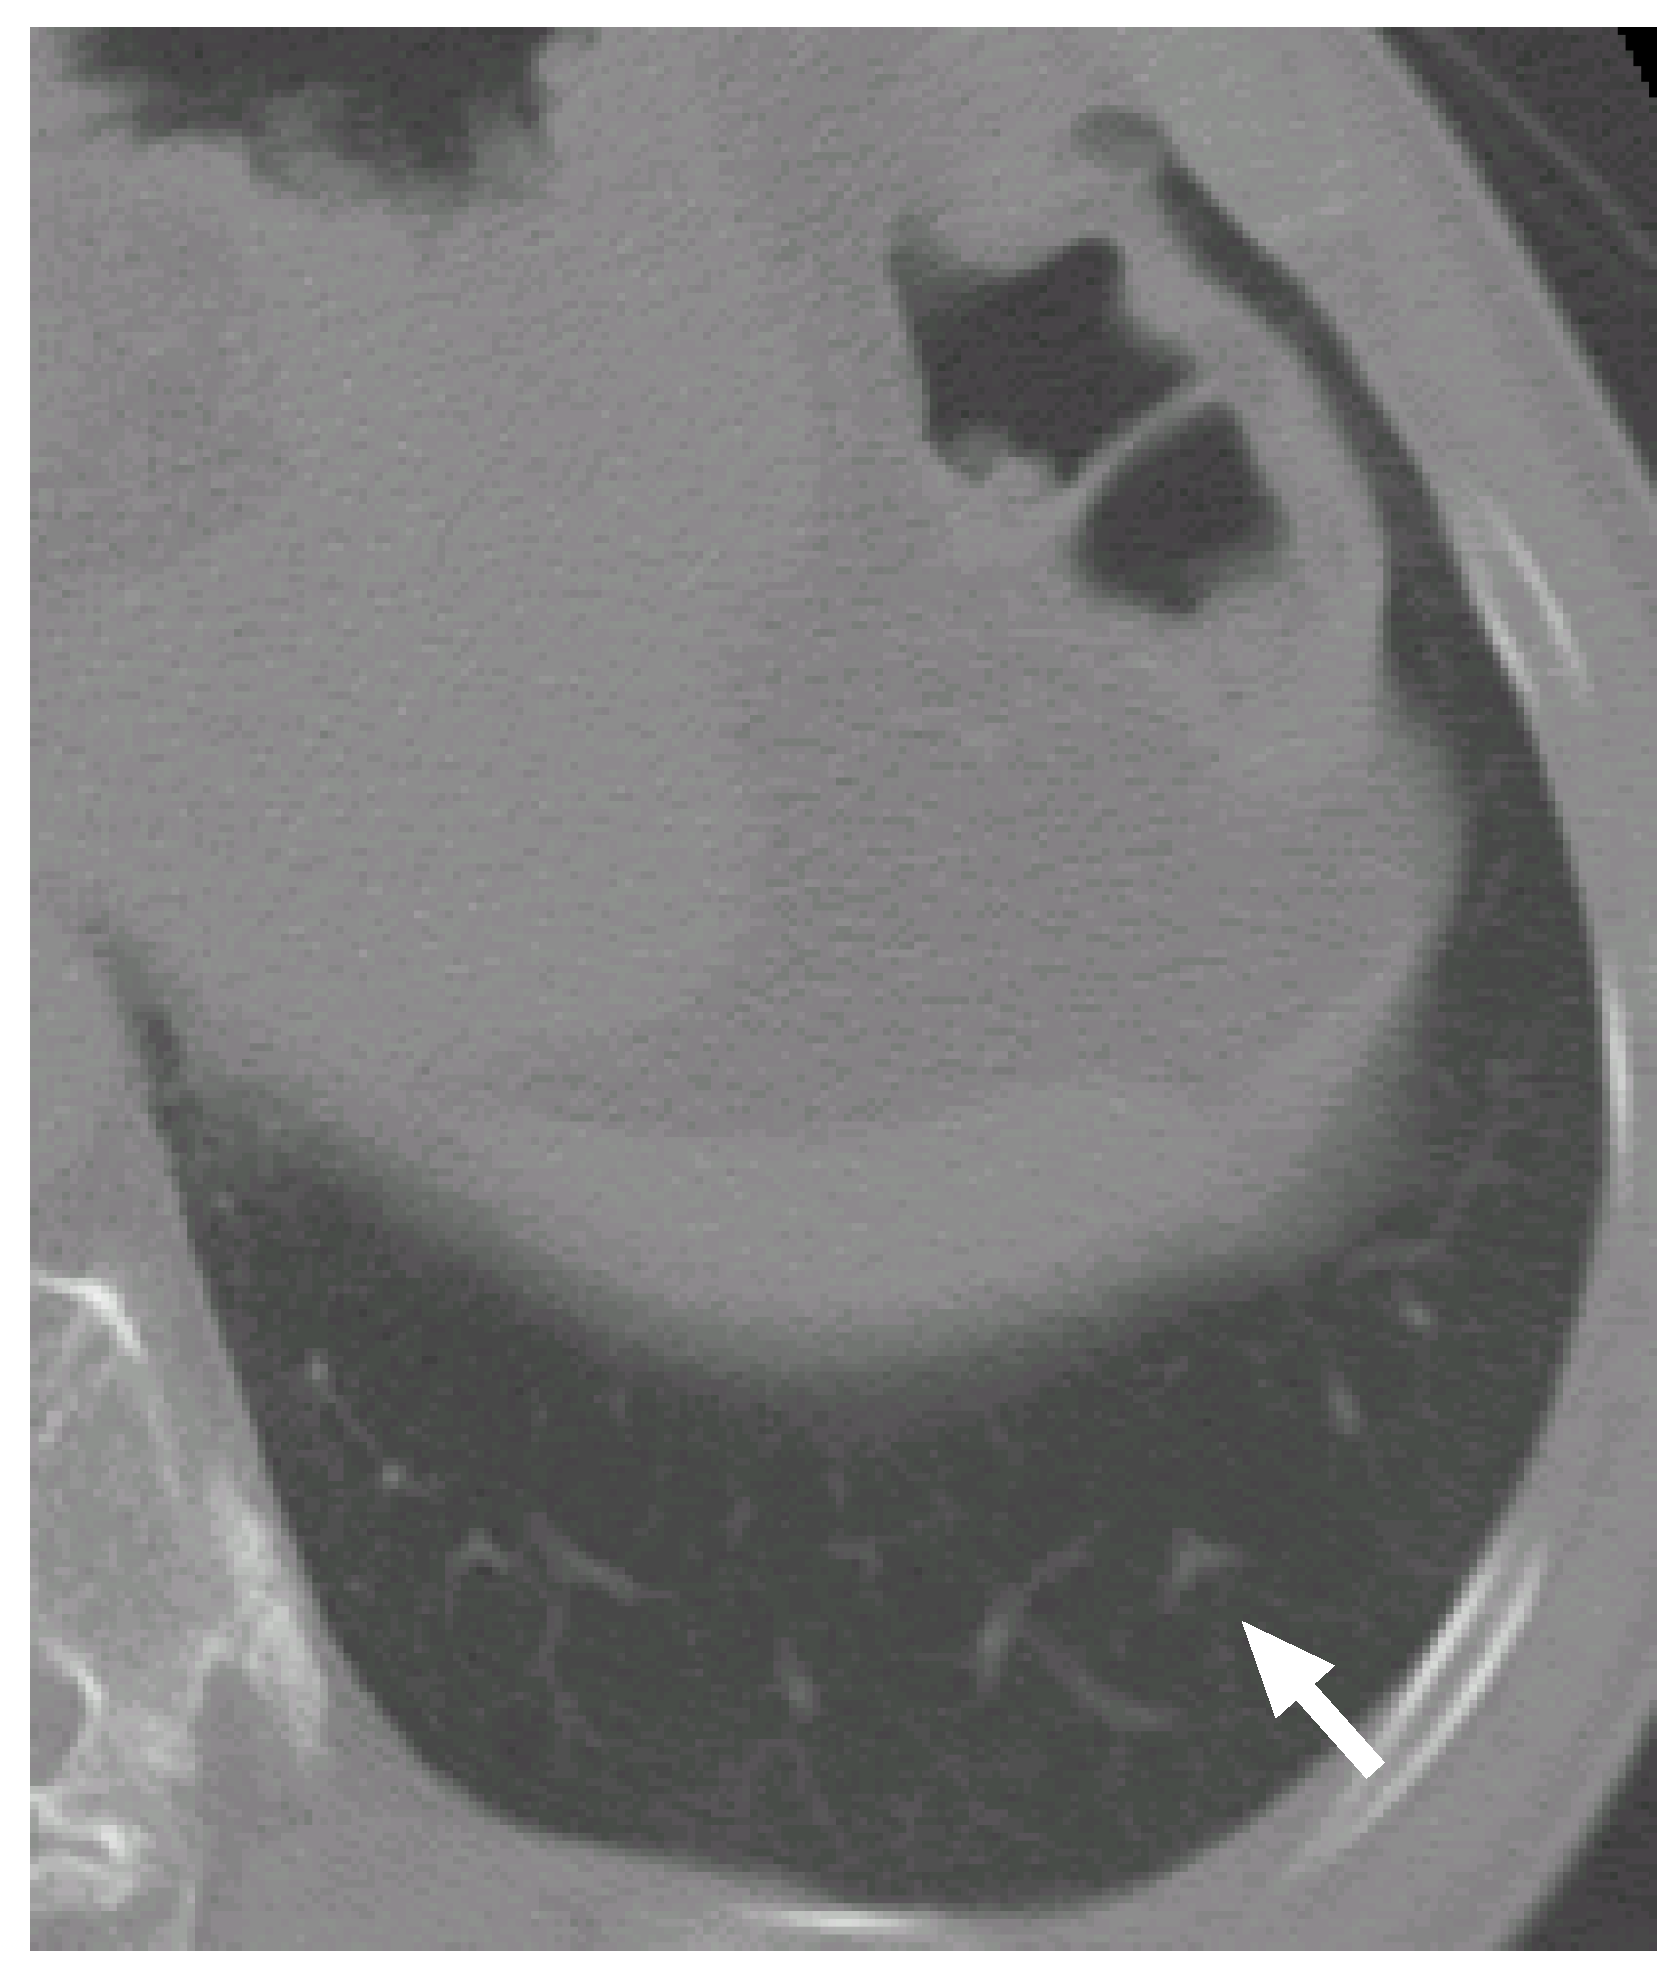

7.3. Case 3

Figure 12 shows another CT scan with a false positive (a bifurcation in a blood vessel tree). Figure 13 shows its VOI and templates, and Figure 14 the most likely object models. The posteriori probabilities are 0.0960, 0.111 and 0.126, and the ratio is 0.762, that is smaller than the threshold. The candidate is correctly determined to be a blood vessel.

The candidate region observed in Figure 13(b) seems to be a nodule that has an irregular shape. It is difficult to recognize the candidate region only from the single slice section. However, by considering the relations between the candidate region and the other regions in the adjacent slice sections, it becomes to be easy to determine that the regions arise from a blood vessel bifurcation.

Figure 12. A bifurcation in a blood vessel tree.